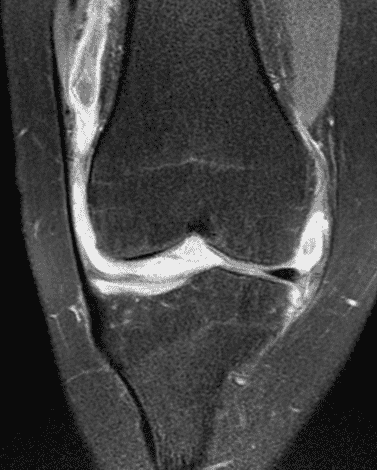

A 19 year-old woman complains of 9 months of unilateral right knee pain and persistent knee swelling without known injury or systemic symptoms. Coronal (1A), sagittal (1B), and transverse (1C) fat-suppressed T2-weighted images of the right knee are provided. What are the findings? What is your differential diagnosis?

Figure 2: (2A) The coronal image shows a large effusion and severe hypertrophic synovitis (asterisks) in the knee. (2B) On the sagittal image the hypertrophic synovium (asterisks) involves the suprapatellar and infrapatellar recesses as well as the anterior and posterior intercondylar notch. A reactive lymph node (arrow) is present in the popliteal fossa. (2C) The axial image demonstrates myositis (arrows) involving the popliteus and peroneus longus muscles. Note the preserved articular cartilage, lack of erosions, and the absence of subcutaneous or marrow edema.